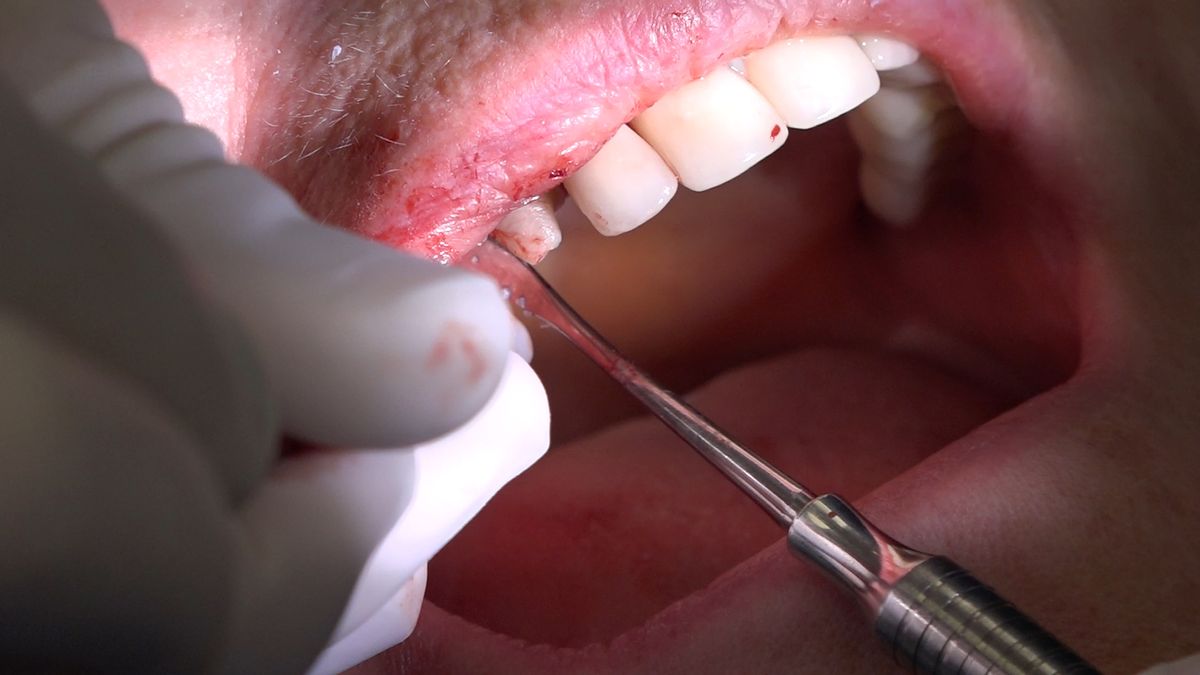

Practiculum Implantologii – Sezon VIIB, sesja 7, dzień 2